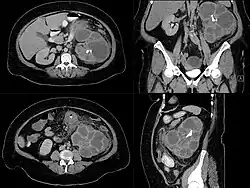

Die Diagnosestellung kann recht schwierig sein, Hauptdifferentialdiagnose ist das Nierenkarzinom. Nicht selten wird die Diagnose erst in der Gewebsuntersuchung gestellt.[2] Im Urinsediment Leukozyturie, Bakteriurie und manchmal Xanthomzellen, im Blutserum Leukozytose, erhöhte BSG und erhöhtes CRP. Teilweise oder komplett tumorartig vergrößerte Niere bei erhaltenem anatomischem Aufbau mit unregelmäßig erhöhter Echogenität im Nierenultraschall, im AUR fehlende oder stark verminderte Ausscheidung.[10] Nierensteine können vorliegen. Die präoperative Abklärung umfasst Computertomografie und/oder Magnetresonanztomographie, letztere bei Kindern und bestehender Niereninsuffizienz.[2][4]